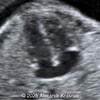

A 33-year-old nullipara with non-contributory medical history presented at 20 weeks, 6 days based on an early scan. Ultrasound revealed the following findings. There were no other apparent abnormalities. What is the most probable diagnosis?